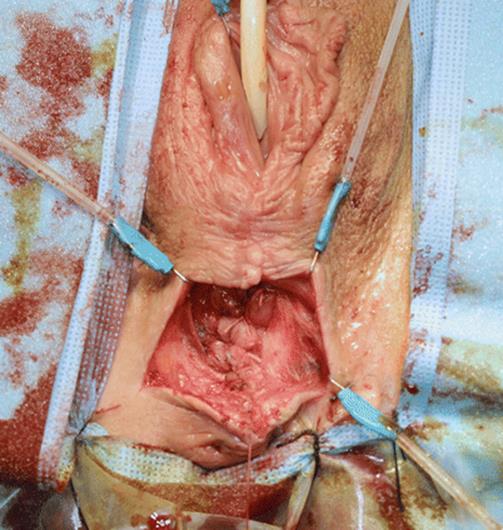

Fig. 8.3

Vaginal examination of the patient with a finger in the vagina under the right labia minora shows the cystic lesion in the inner aspect of the labia